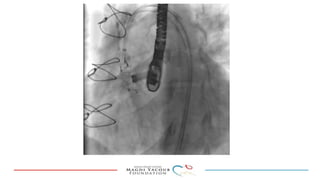

This document provides an overview of percutaneous prosthetic valve leakage (PVL) closure, including indications, approaches, techniques, and closure devices. It discusses that over 210,000 prosthetic valve surgeries are performed each year, with PVL occurring in some cases. While surgical closure has a high mortality rate, percutaneous closure has a procedural success rate of 86% and less complications. Indications for closure include symptomatic heart failure, hemolysis, rocking prosthesis, or leaks over 30% of the sewing ring. Techniques discussed include retrograde and transapical approaches using devices like the Amplatzer and Occlutech plugs. A team approach and techniques like sequential deployment are emphasized for